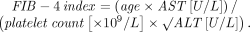

FIB-4 index for HCV, NAFLD

The FIB-4 index predicts the presence of advanced fibrosis using, as its name indicates, a combination of 4 factors in fibrosis: age, platelet count, and the levels of aspartate aminotransferase (AST) and alanine aminotransferase (ALT), according to the formula:

The index was derived from data from 832 patients co-infected with HCV and human immunodeficiency virus.24 The Ishak staging system10 for fibrosis on liver biopsy was used for confirmation, with stage 4 to 6 defined as advanced fibrosis. A cutoff value of more than 3.25 had a positive predictive value of 65% for advanced fibrosis, and to exclude advanced fibrosis, a cutoff value of less than 1.45 had a negative predictive value of 90%.

The FIB-4 index has since been validated in patients with HCV infection25 and NAFLD.26 In a subsequent study in 142 patients with NAFLD, the FIB-4 index was more accurate in diagnosing advanced fibrosis than the other noninvasive prediction models discussed below.27